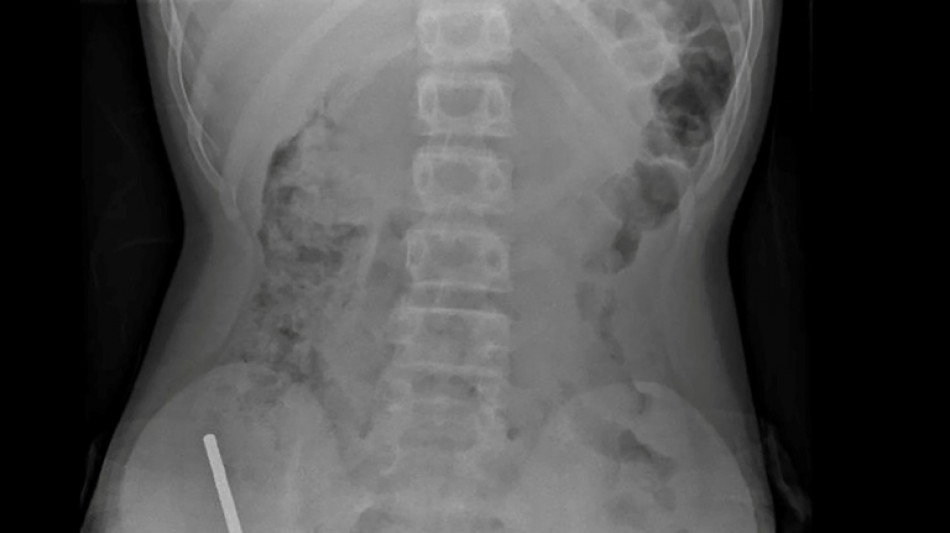

Nouvelle-Zélande: un adolescent opéré après avoir ingéré près de 100 aimants achetés sur Temu / Photo: Handout - NEW ZEALAND MEDICAL JOURNAL (NZMDJ)/AFP

En Nouvelle-Zélande, un adolescent de 13 ans s'est vu retirer plusieurs parties nécrosées de ses intestins après avoir avalé près d'une centaine d'aimants achetés en ligne sur le site Temu, a rapporté vendredi une revue médicale.

Après avoir souffert de douleurs abdominales pendant quatre jours, l'adolescent a été transporté à l'hôpital de Tauranga, sur l'île du Nord.

"Il avoué avoir ingéré entre 80 et 100 aimants puissants au néodyme, de 5x2mm environ, une semaine plus tôt", indique un rapport des médecins de l'hôpital de cet hôpital, publié dans le New Zealand Medical Journal (NZMJ).

Ce type d'aimants, interdit en Nouvelle-Zélande depuis janvier 2013, aurait été acheté sur la plateforme chinoise d'e-commerce Temu.

Les médecins ont déclaré que la pression exercée par les aimants avait provoqué une nécrose dans quatre zones de l'intestin grêle et du gros intestin du garçon.

Il a été opéré afin que l'on lui retire les aimants et les tissus nécrosés, et il a pu rentrer chez lui après huit jours à l'hôpital.